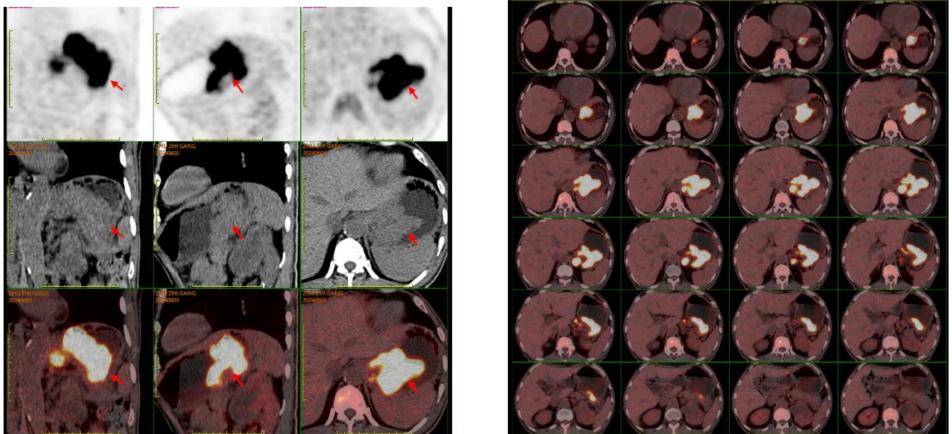

PET/CT:贲门部、胃底部及胃体部胃壁增厚、局部软组织密度肿物形成,葡萄糖代谢增高,考虑恶性可能性大(胃癌?)。肝胃之间多发葡萄糖代谢增高淋巴结,考虑转移可能大。左肾上极混杂密度肿物,内伴钙化及坏死,葡萄糖代谢增高,考虑恶性可能性大(肾癌?)。

疗效评估:复查影像学显示贲门胃小弯侧肿瘤、肝胃间隙转移淋巴结及左肾占位均较前缩小。